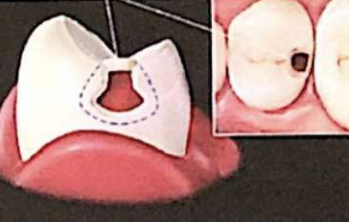

- Préparation des tunnels pour Classe II : Les caries proximales sont abordées par un tunnel depuis la surface occlusale, terminant sur la lésion proximale sans couper la crête marginale.